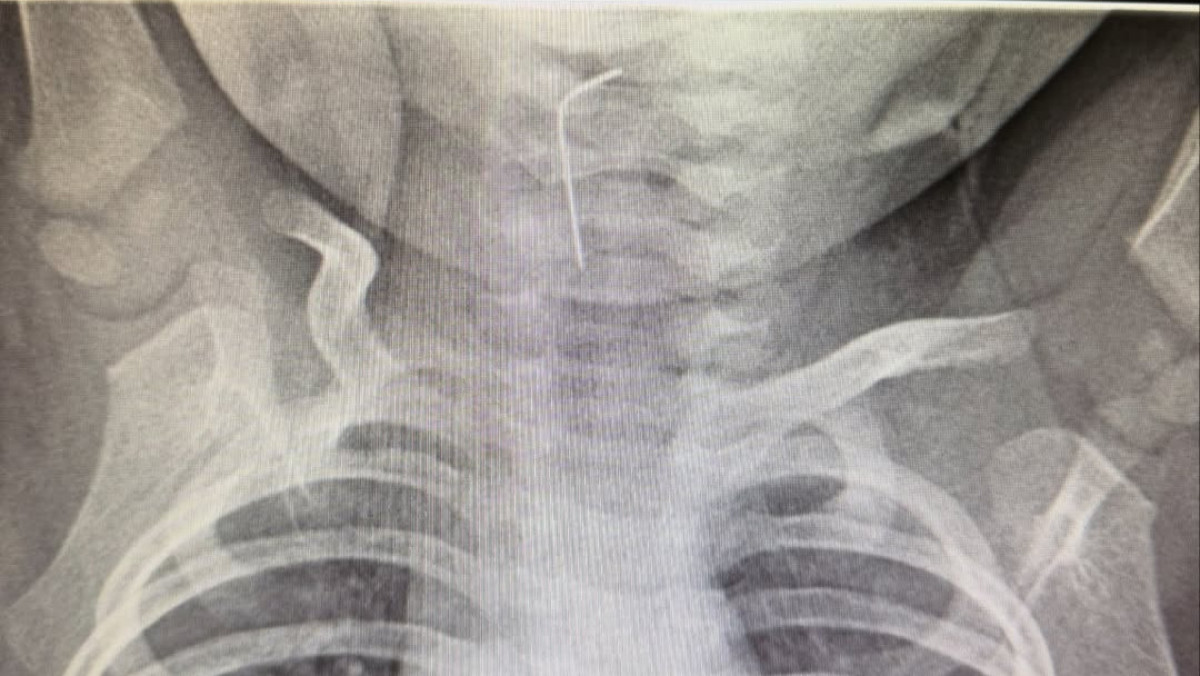

Фото: Түркістан облысының Денсаулық сақтау басқармасы

Түркістанда өңешіне ине тұрып қалған сәбиге көмек көрсетілді.

Түркістан облыстық балалар ауруханасына жедел жәрдем қызметі арқылы 9 айлық сәби шұғыл түрде жеткізілді.

Белгілі болғандай, сәби абайсызда ине жұтып қойған. Тез арада аурухана мамандары - хирург Темірбеков Мұхагали және эндоскопист Ырысқұлов Бабыр эндоскопиялық әдісті қолдана отырып, рентгенологиялық тексеру жүргізді. Нәтижесінде бөгде заттың нақты орналасқан орнын анықтап, өңеште тұрып қалған бөгде затты сәтті түрде алып шықты, - деп хабарлады Түркістан облысы әкімдігінің баспасөз қызметі.

Медициналық көмек жедел әрі кәсіби көрсетілуінің нәтижесінде ықтимал асқынулардың алдын алу жұмыстары сәтті аяқталды.

Дәрігерлердің айтуынша, қазіргі таңда баланың жағдайы жақсы. Сәби дәрігерлердің бақылауында болып, үйіне шығарылды.